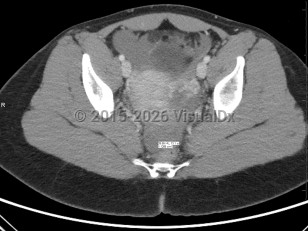

A 2011 consensus statement provides definitions that draw attention to the complexity of evaluating for and diagnosing ectopic pregnancy, with 5 categories based on sonographic findings:

- Definitive intrauterine pregnancy

- Probable intrauterine pregnancy

- Pregnancy of unknown location

- Probable ectopic pregnancy

- Definite ectopic pregnancy